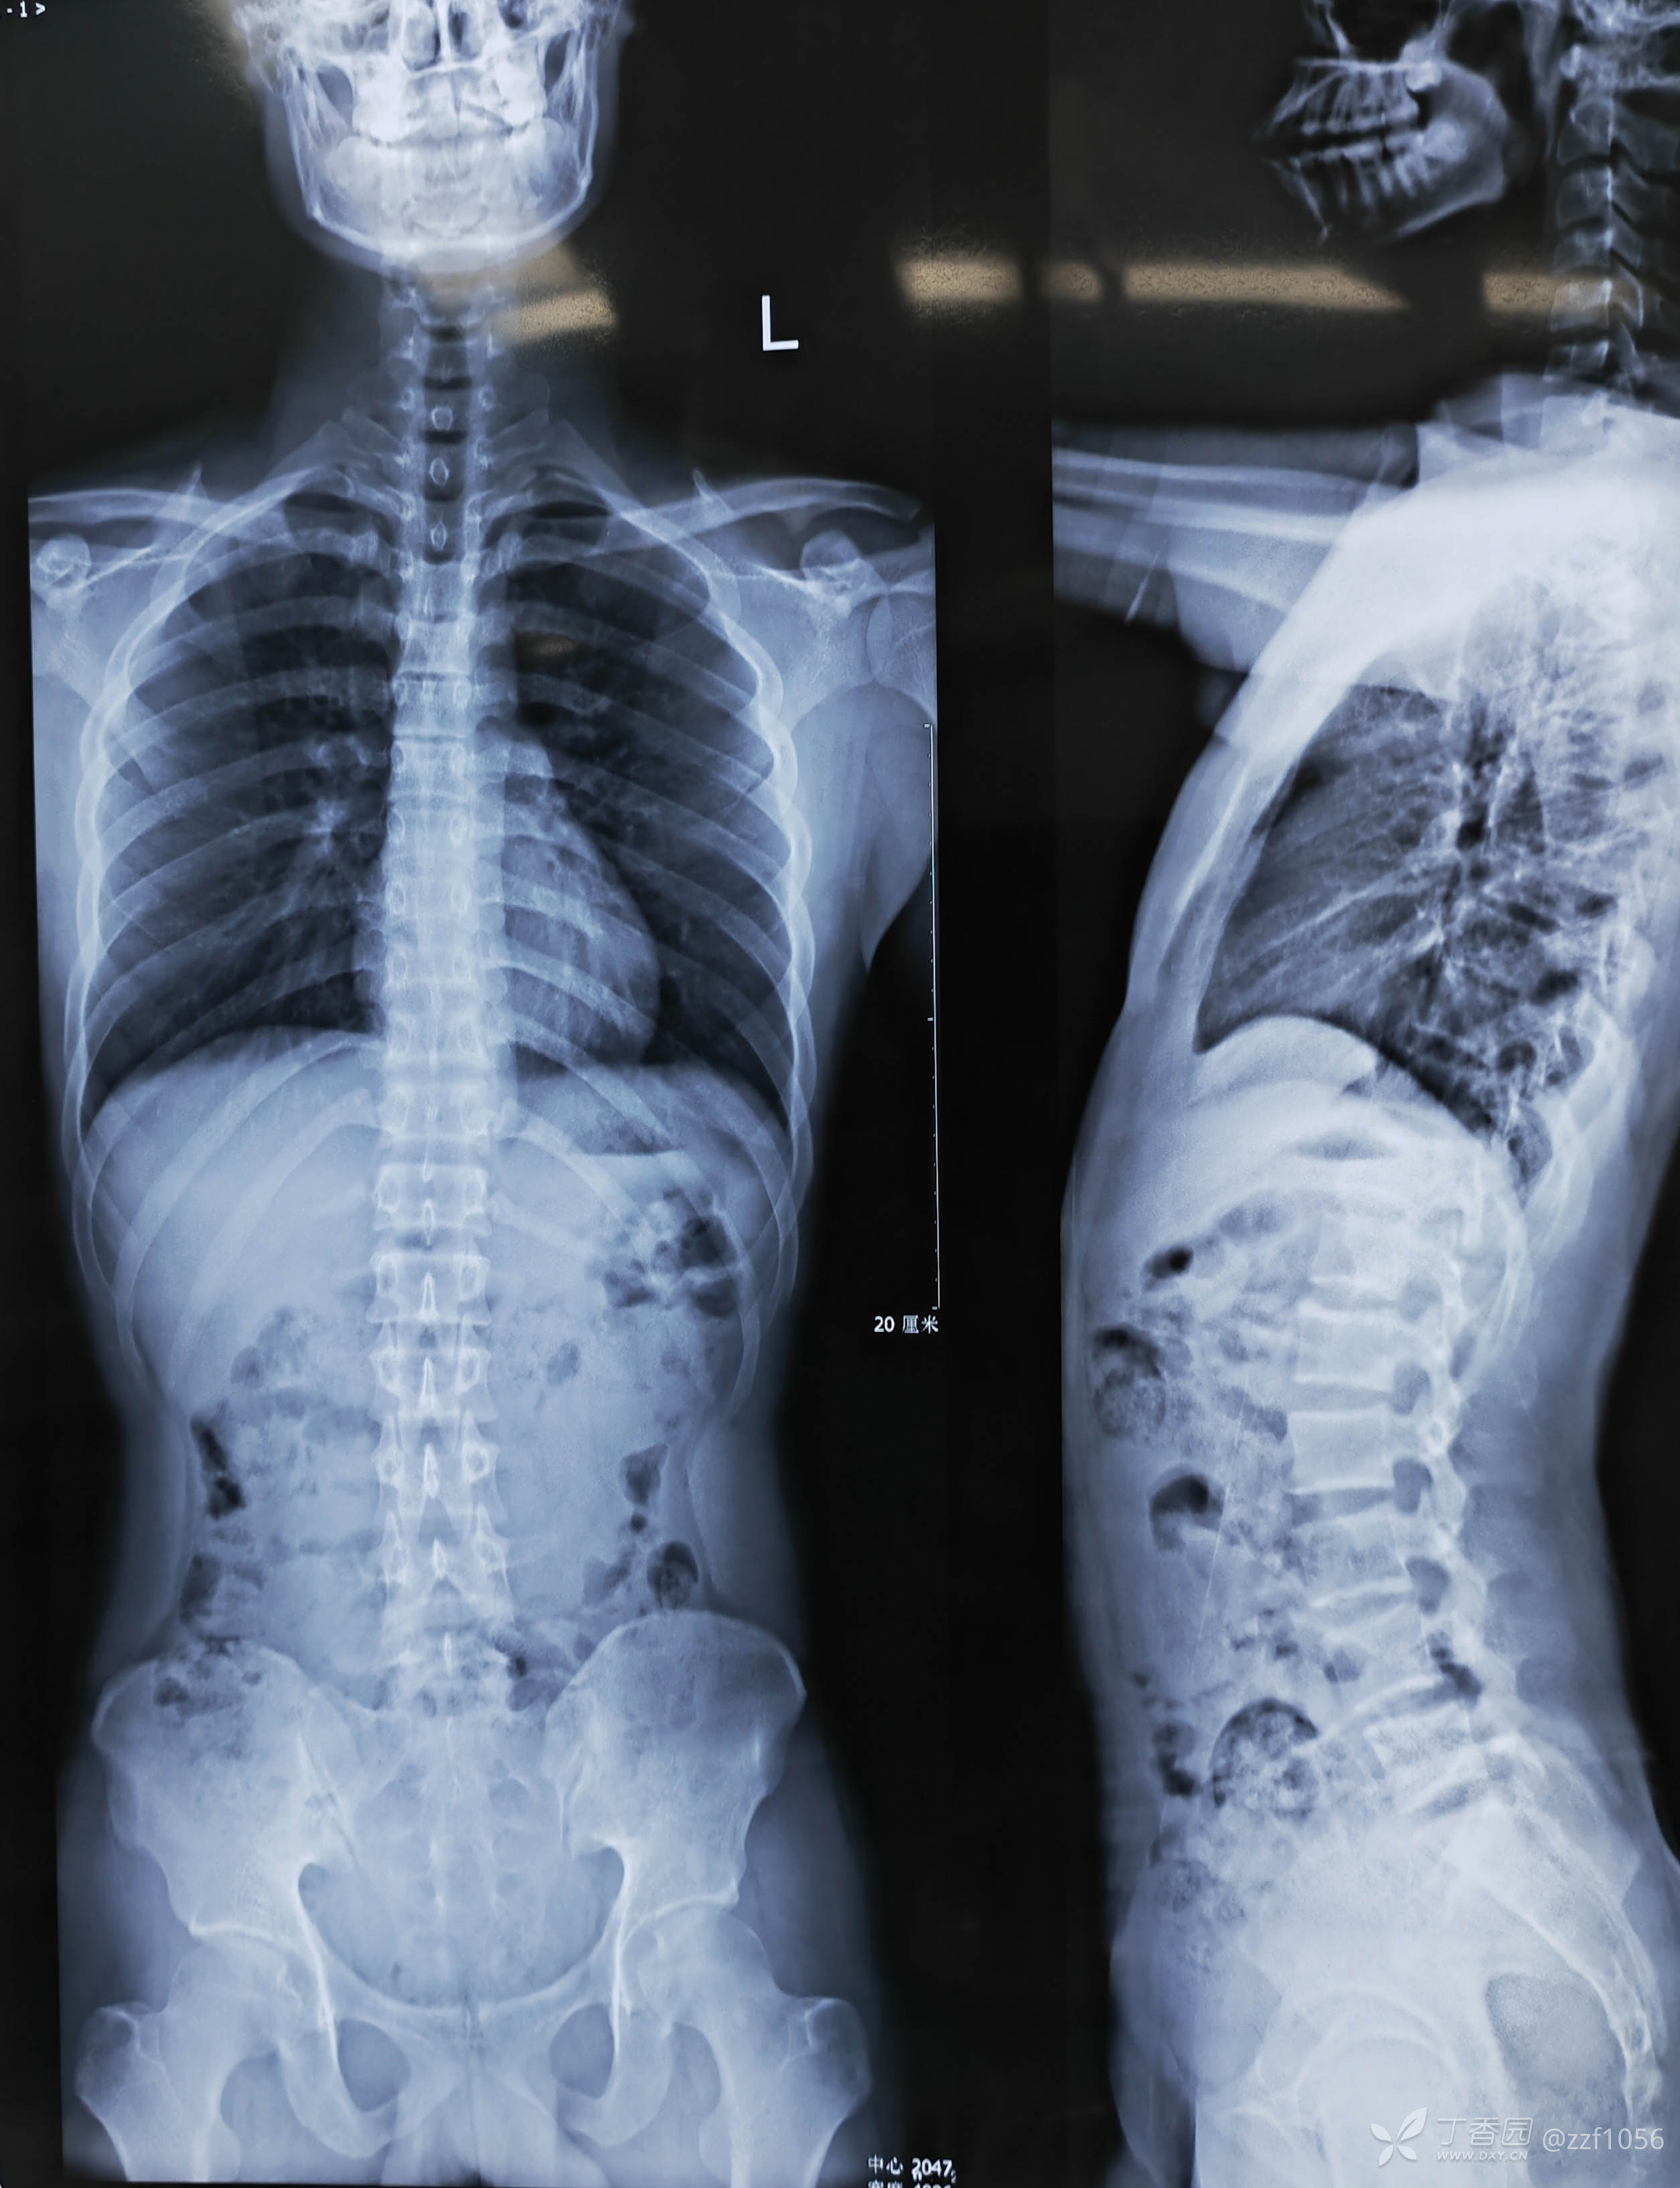

患者男,19岁,高三学生,左下肢疼痛半年,各种保守治疗无效

体育特长生,平时举杠铃蹲卧训练,平素体健

入院诊断:腰椎间盘突出症(L4/5)

虽然能够选择性微创,年轻化与复发也是个问题